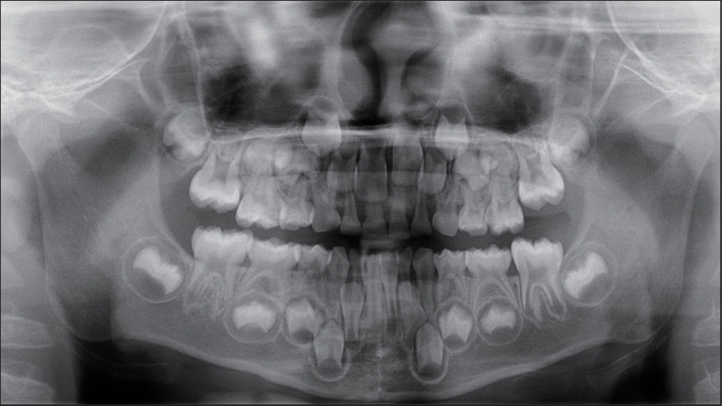

目的 应用口腔全景曲面体层片研究乳尖牙双根的发生率和特征。 方法 收集3~9岁儿童的口腔全景曲面体层片,共纳入100 976张,观察记录乳尖牙双根的发生情况和分布规律。应用SPSS 25.0统计软件分析所得的数据。查阅乳尖牙双根的报道文献,记录患者资料。 结果 乳尖牙双根的发生率为0.37‰(37/100 976),其中男性发生率为0.59‰(32/54 276),女性发生率为0.12‰(5/46 700),男女间差异有统计学意义(χ2 =15.955,P=0.000)。37例儿童的乳尖牙双根发生数目以1~2颗为主,其中1颗者11例(29.73%),2颗者18例(48.65%)。76颗乳尖牙双根的牙位分布左侧和右侧间差异无统计学意义(χ2 =1.316,P=0.251),上颌和下颌间差异有统计学意义(χ2 =15.213,P=0.000),单侧和双侧间差异有统计学意义(χ2 =6.083,P=0.014)。 结论 乳尖牙双根罕见,发生数目多为1~2颗,男性多于女性,上颌多于下颌,双侧发生多于单侧发生。

Objective The incidence and clinical characteristics of bi-rooted primary canines were investigated by performing oral panoramic radiographs. Methods A total of 100 976 oral panoramic radiograph of subjects aged 3-9 years old were collected, and the incidence and distribution of bi-rooted primary canines were observed and recorded. The obtained data were analyzed using SPSS 25.0 statistical software, and the literature on bi-rooted primary canine was reviewed to record patient’s data. Results The incidence of bi-rooted primary canines was 0.37‰ (37/100 976), of which 0.59‰ (32/54 276) occurred in males and 0.12‰ (5/46 700) in females. Statistically significant difference was observed between males and females (χ2 =15.955, P=0.000). The number of bi-rooted primary canine in 37 children was mainly 1-2. Among them, 11 subjects (29.73%) had one bi-rooted primary canine, and 18 subjects (48.65%) had two bi-rooted primary canines. The tooth position distribution of 76 bi-rooted primary canines showed no significant difference between the left and right sides (χ2 =1.316, P=0.251). However, significant difference was found between the upper and lower jaws (χ2 =15.213, P=0.000) and between the unilateral and bilateral sides (χ2 =6.083, P=0.014). Conclusion Bi-rooted primary canines are rare, mostly occur in 1-2 teeth, and are more common in males than females, in the upper jaw than in the lower jaw, and on both sides than on one side.